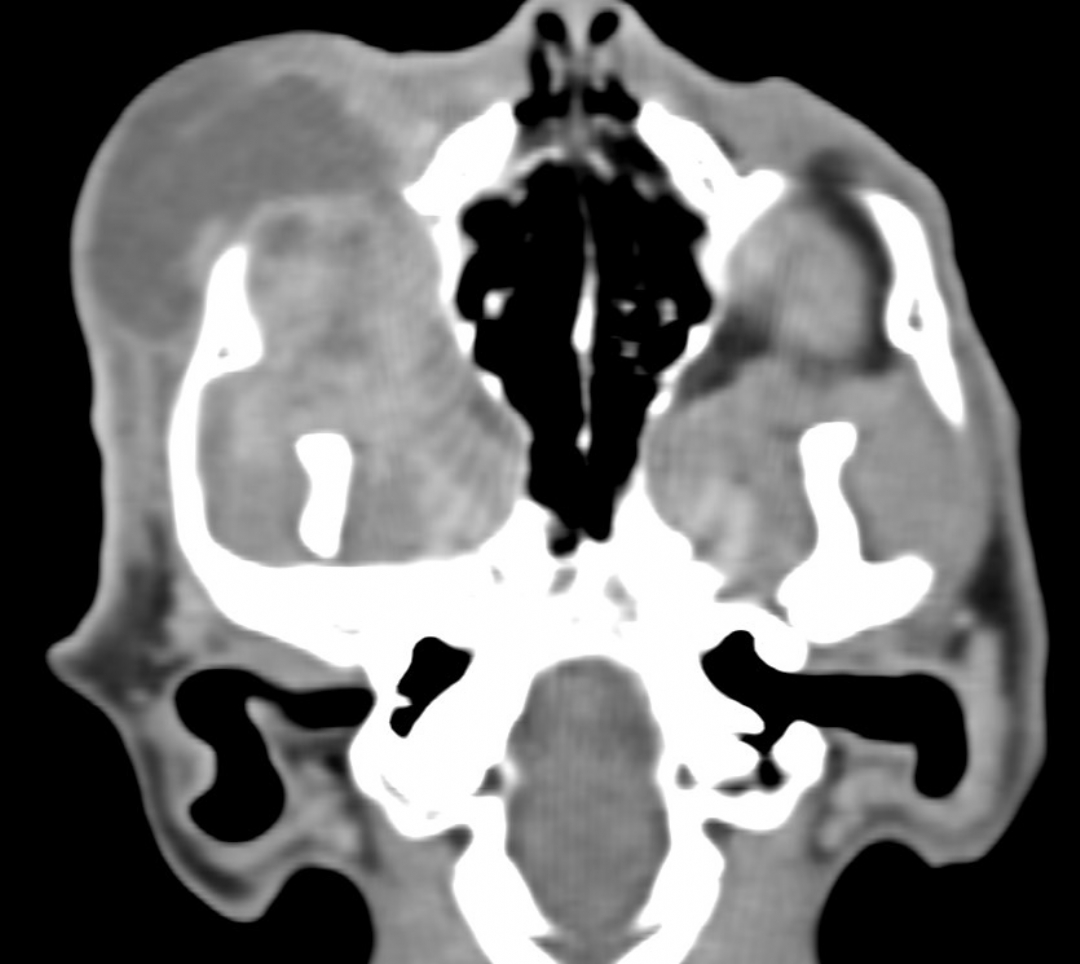

眼周團塊、定位病灶、採樣、評估治療計畫

右上顎腫脹、採樣、評估治療計畫

鼻腔疾病、鼻腔鏡探查、採樣、評估治療計畫